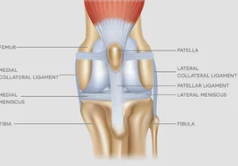

1. 슬개골탈구란?

슬개골탈구는 무릎 뼈(슬개골)가 정상 위치에서 벗어나 바깥쪽이나 안쪽으로 밀려나는 질환입니다.